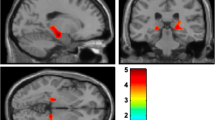

Lowest specific to non-displaceable binding ratio (SBR), putamen (relative) asymmetry index (AIput), and the absolute difference between left and right SBR are shown in Fig. 1. Lowest putamen SBRs were similar in PDRBD+ compared to PDRBD− (p = 0.7, median 0.93 vs. 0.82). There was no significant difference in AIput between PDRBD+ and PDRBD− (p = 0.97, median 0.13 vs. 0.14).

Lowest putamen SBR (a) and putamen DAT asymmetry index (b) plotted per group, with medians indicated by horizontal bars.One outlier for the putamen in each PD group is indicated by a black star, AIput = 1.06 for the PDRBD+ and AIput = 0.69 for the PDRBD− patient. The iRBD patients with an abnormal DAT scan (n = 9) have been plotted in dark blue, with the rest of the iRBD patients shown in light blue (n = 8). Additionally, c shows the absolute difference between left and right putamen SBR, and d the difference in left and right UPDRS-III motor scores (here, the total iRBD group, n = 20, is shown).

17 out of the 20 iRBD patients underwent DAT SPECT imaging, where the group was split based on the DAT scan being evaluated as either normal (iRBDnorm, n = 8) or abnormal (iRBDpath, n = 9). The median lowest putamen SBR was 2.4 in iRBDnorm and 1.6 in iRBDpath, with the difference being significant (p < 0.0001). We did not directly compare the SBRs between the iRBD and PD groups due to differences in camera and processing pipelines. Furthermore, we did not compare the relative asymmetry index AIput between groups with significantly (or apparently) differing SBRs. The motivation for this is further treated in the Discussion, see also Supplementary Fig. 3 in the Supplementary Information. Instead, we statistically evaluated the differences in absolute asymmetry.

Considering the absolute difference between the highest and lowest putamen SBR (Figure 1c), the median was 0.33 for PDRBD+, 0.22 for PDRBD-, 0.23 for iRBDpath and 0.05 for iRBDnorm. There was, again, no significant difference between PDRBD− and PDRBD+ considering this alternative measure for asymmetry (p = 0.4). Notably, iRBDpath was not significantly different from either PDRBD+ (p = 0.08) or PDRBD− (p = 0.93) with this measure. iRBDnorm had a significantly lower absolute difference than PDRBD+ (p = 0.002) but was not significantly different from PDRBD− (p = 0.06) or iRBDpath after Bonferroni correction (p = 0.03).

We used an exploratory cutoff of AIput = 0.08 to estimate the fraction of patients showing symmetric versus asymmetric degeneration in each group, corresponding to the upper quartile reported in AIput for HC subjects of the PPMI database in ref. 22. Considering this cutoff, all subjects in iRBDnorm fell below the threshold, while 33% in iRBDpath, 68% in PDRBD+ and 63% in PDRBD− were asymmetric.

Motor asymmetry

The distributions of motor asymmetry index AImotor, as described by the absolute difference between left and right scores of the UPDRS-III scale can be seen in Figure 1d. There was no difference in AImotor between PDRBD+ and PDRBD− (median 2 vs. 4, p = 0.3). Both PD groups were more asymmetric than the iRBD patients (p < 0.02 for both).